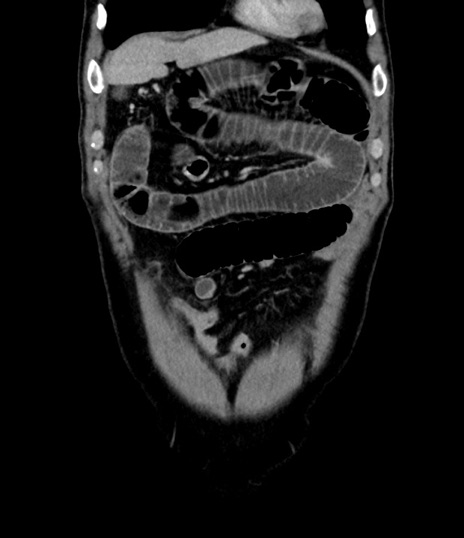

症例8(冠状断像)

【症例】 60歳代男性

【主訴】 黒色吐物

【現病歴】 4日前から嘔気自覚、2日前の朝食後にも嘔気あり、自分で手で嘔吐反射起こし嘔吐したところ血が混ざっていたため受診。

【既往歴】 5年前汎発性腹膜炎を伴う急性虫垂炎で手術、高血圧、前立腺肥大症、高脂血症

【身体所見】 腹部正中に手術癩痕あり 腹部平坦・軟圧痛なし膨満感あり

【データ】WBC 8400、CRP 4.54